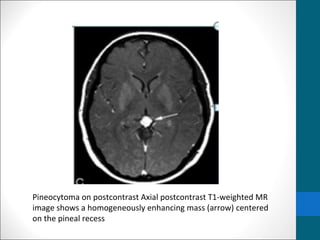

Pineocytoma on postcontrast Axial postcontrast T1-weighted MR

image shows a homogeneously enhancing mass (arrow) centered

on the pineal recess

Pineocytoma on postcontrastAxial postcontrast T1-weighted MR image shows a homogeneously enhancing mass (arrow) centered on the pineal recess